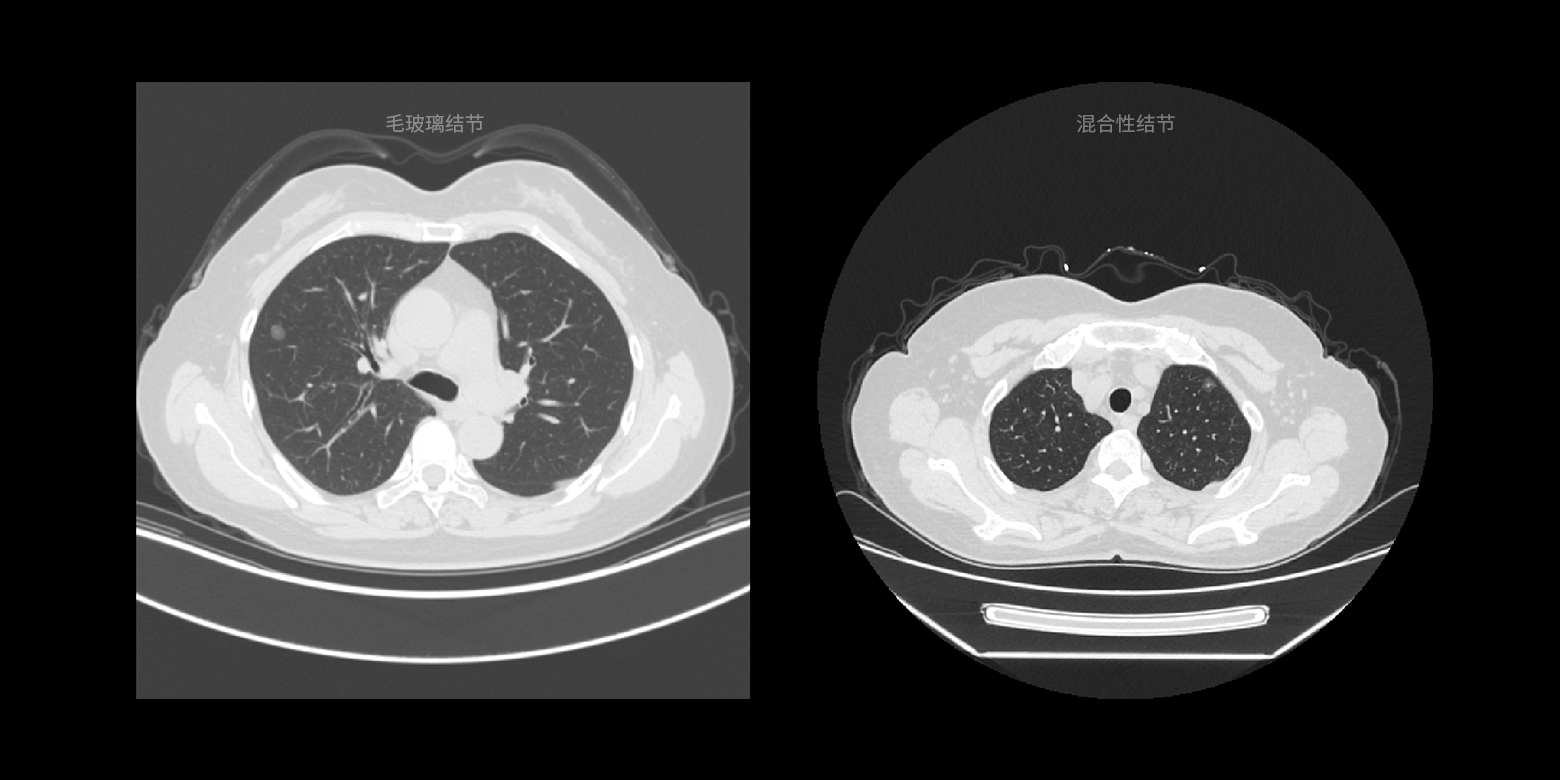

• 03病灶良恶性鉴别与疾病分级

病灶类型鉴别

结合国际通用的诊断指南以及顶级医生的诊断经验,对临床诊断起到关键作用的病灶类型进行快速鉴别,降低相似病灶的误诊概率。